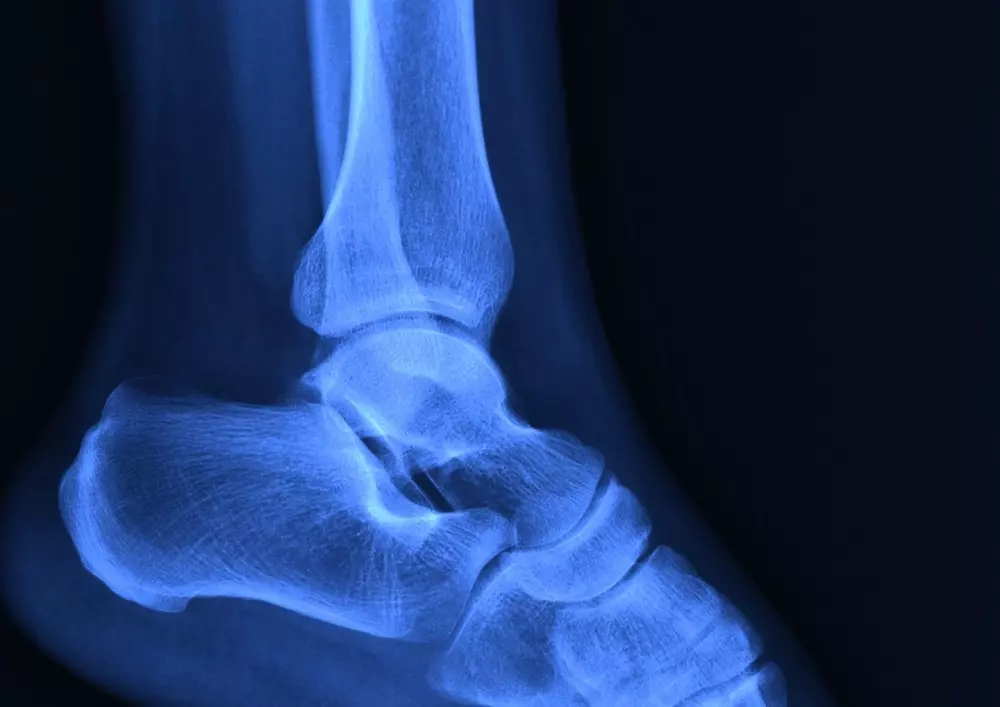

Zespolenie śródszpikowe – postępowanie fizjoterapeutyczne po usunięciu zespolenia

W rubryce „Z praktyki gabinetu” omawiamy zagadnienie, jakim jest zespolenie śródszpikowe. To rodzaj zespolenia stosowanego podczas osteosyntezy stabilnej zewnętrznej. Polega ono na wprowadzeniu do jamy szpikowej gwoździ, śrub czy prętów. Przedstawiamy także rehabilitację 57-letniej pacjentki po złamaniu trójkostkowym z podwichnięciem stopy i po usunięciu zespolenia śródszpikowego. Ponadto w tekście autorzy opisują uraz, jakim jest złamanie wraz z objawami, diagnostyką i leczeniem, a także procesem gojenia złamań.